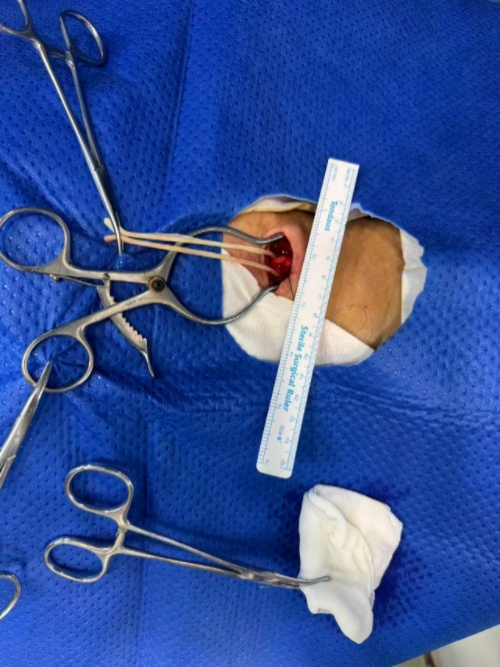

二、颈部入路与颈动脉穿刺

1. 切口与暴露

沿标记做横切口,逐层切开皮肤、皮下、颈阔肌,分离至颈动脉鞘。

纵行切开颈动脉鞘,游离颈总动脉近端(距分叉≥5cm),用血管吊带控制近、远端,美兰标记穿刺点(避开斑块)。

2. 微穿刺与鞘管置入

微穿针穿刺颈总动脉,送入0.014in导丝,交换置入微血管鞘。

经微血管鞘送入0.035in J形导丝至颈外动脉远端,撤出微鞘,导入TCAR专用动脉鞘(置于病变近端2cm处)。

撤出导丝与扩张器,排尽鞘管内空气,连接Y型阀与管路系统。

2. 颈部止血与缝合

颈部穿刺点压迫止血(或用血管缝合器闭合),逐层缝合颈阔肌、皮下、皮肤,敷料覆盖。